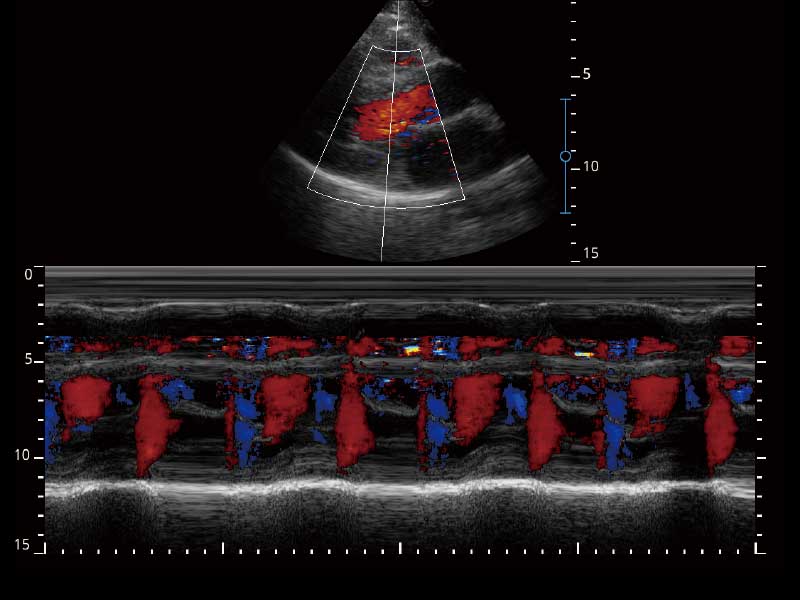

μ-Scan微米成像、空间复合成像、高分辨率血流成像。